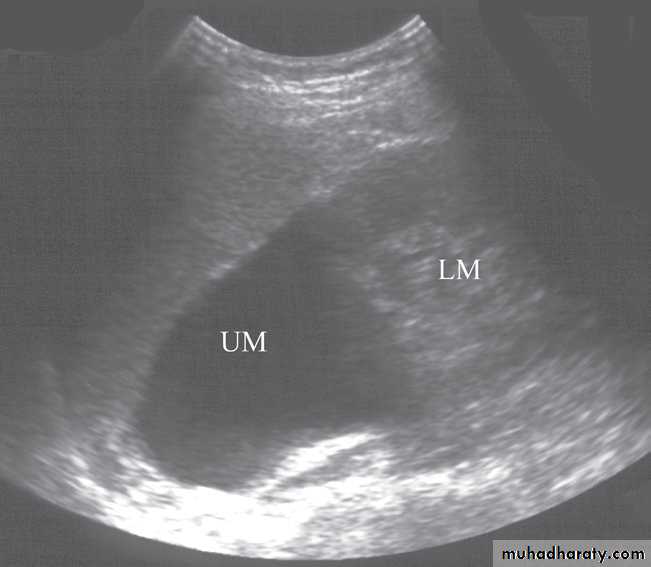

The bladder is well demonstrated on all imaging modalities. At ultrasound, the simplest routine method of imaging, the bladder lumen should be free of echogenic structures and its wall should be of uniform thickness .Bladder tumours

The bladder is the most frequent site for neoplasms in the urinary tract . Almost all are transitional cell carcinomas of varying degrees of malignancy.On ultrasound examination

bladder tumours are seen as soft tissue masses protruding into the fluid-filled bladder or as localized bladder wall thickening, . On rare occasions, there is visible calcification on the surface of the tumour, but the technique is poor for detecting extravesical spread.